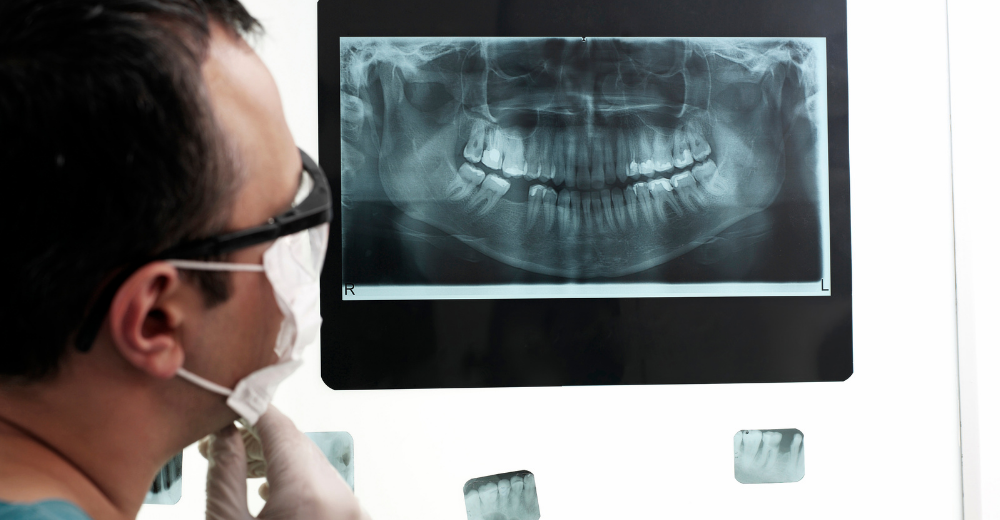

L’Esame RX Emimandibola, conosciuto anche come radiografia emimandibolare, è un esame radiologico che permette di ottenere immagini dettagliate della mandibola, dei denti e delle articolazioni temporo-mandibolari. Questa indagine è particolarmente utile per visualizzare in modo chiaro e preciso eventuali fratture ossee, dislocazioni, infezioni o cisti presenti nella mandibola.

Durante l’esame, il paziente viene posizionato davanti all’apparecchiatura radiologica. Un supporto apposito viene utilizzato per stabilizzare la mandibola, consentendo l’acquisizione di immagini chiare e precise. I raggi X emessi attraversano i tessuti molli del viso e vengono assorbiti dalle strutture ossee, generando immagini che vengono successivamente analizzate dal radiologo o dallo specialista in odontoiatria del Poliambulatorio S-Medical Group di Sora.

Quali Patologie Possono Essere Evidenziate con l’Esame RX Emimandibola?

L’Esame RX Emimandibola è particolarmente efficace nell’individuare diverse condizioni patologiche e anormalità strutturali della mandibola. Tra queste troviamo: